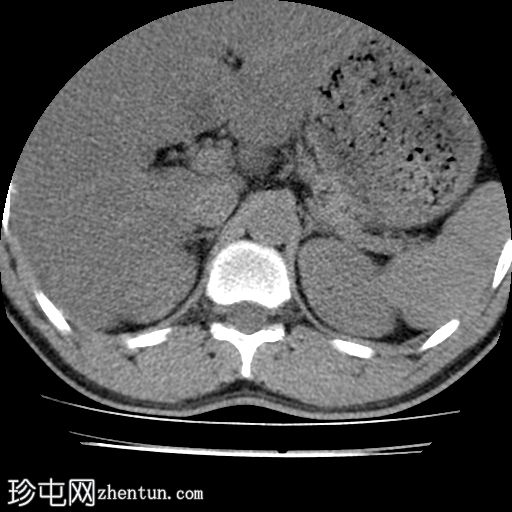

轴位肾脏

8.jpg